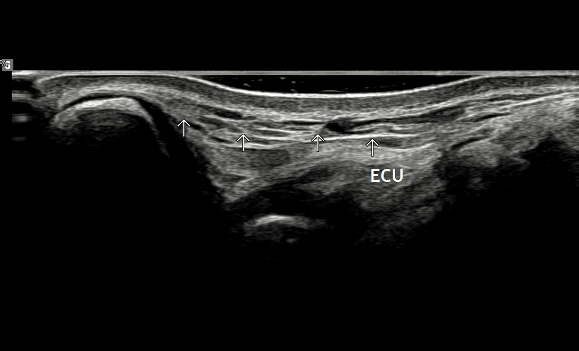

- 치료기간 : 25 . 6 . 9 ~ 25 . 10 .27

- 치료횟수 : 4 사이클(20) 회

치료전

치료 후

힘줄 두께 감소 및 전체적인 파열 부위 축소 & 골극 감소

-> 검사상 파열은 여전히 있지만 운동 이후에도 통증이 크게 없어서 치료 종료 후 3~4주정도 텀 두고 관찰 예정